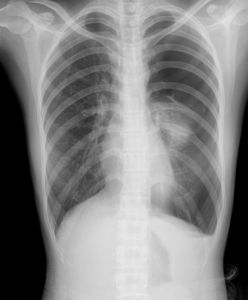

X線檢查:氣胸的典型X線為肺向肺門萎陷呈圓球形陰影,氣體常聚集於胸腔外側或肺尖部,此部透亮度增加,無肺紋。氣胸延及肺下部時肋膈角顯示銳利。少量氣胸時積氣多局限於肺尖,易被鎖骨影遮掩。此時,深呼氣相的X線徵象有助於診斷。部分自發性氣胸患者由於胸膜粘連分隔而呈現為“局限性氣胸”,積氣影可能被肺或縱隔遮掩,需轉動體位透視檢查方能發現。

1.X線檢查是診斷氣胸最可靠的方法,可顯示肺萎縮程度、有無胸膜粘連、縱隔移位及胸腔積液等。氣胸側透明度增強,無肺紋理,肺萎縮於肺門部,和氣胸效界處有清楚的細條狀肺邊緣,縱隔可向健側移位,尤其是張力性氣胸更顯著;少量氣胸則占據肺尖部位,使肺尖組織壓向肺門;如有液氣胸則見液平面。

3.胸腔積液 胸腔積液患者也常表現為胸痛和氣促,但體檢和X線檢查為積液征而別於氣胸。

4.心肌梗死、肺梗死張力性氣胸臨床表現有時酷似心肌梗死、肺梗死,都表現為突發劇烈胸痛、氣促、呼吸困難、心慌、面色蒼白或發紺、大汗、煩躁不安等,但張力性氣胸患側明顯的胸腔積氣征和氣管對側移位有助於鑑別,X線檢查及人工氣胸機診斷性穿刺可確診。